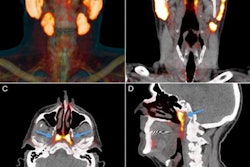

Shao presented his team’s combined deep learning approach for opportunistic PGT detection of CT. The researchers focused on improving complementary objectives for tumor screening and segmentation.

The team employed a multistage deep-learning pipeline to optimize its model for PGT detection. Here, an initial model localizes each parotid gland. At the same time, a single 3D U-Net model implements segmentation and screening tasks. The researchers calibrated thresholds for positive voxel predictions to convert segmentation outputs into binary screening results.